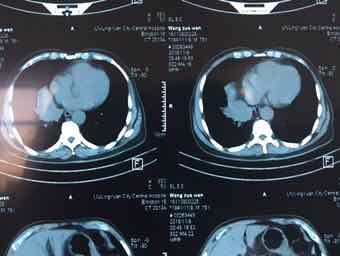

男,74岁,咳嗽咳痰3个月,无发热,无胸痛,无盗汗,无咳血。右肺占位性质待查?完善气管镜检查